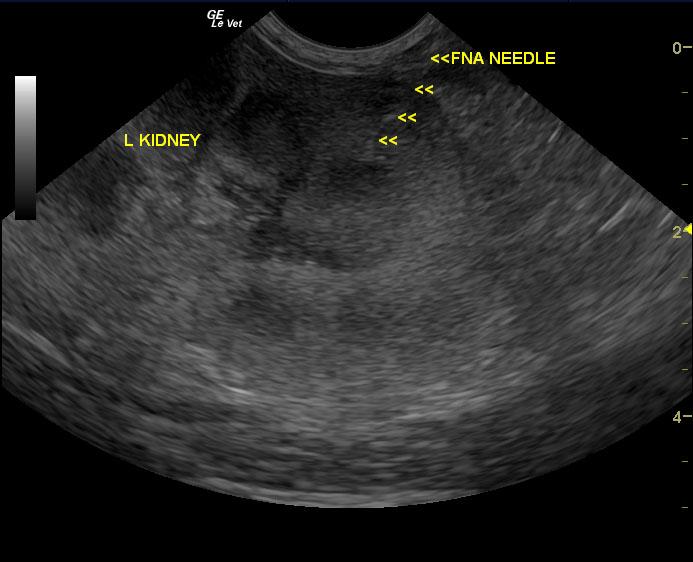

A seven-year-old MN DSH cat was presented with lethargy with the owner reporting that the cat’s behavior and temperament had changed. On urinalysis the urine was straw in color and clear; USPG was inappropriate (1.021), hematuria was present. The urine protein/creatinine ratio was 1.1. Abnormalities on CBC and serum chemistry were anemia, neutrophilia, lymphopenia, monocytosis, hypoproteinemia, and azotemia. Abdominal radiographs revealed an left nephromegaly and a mass effect in the gastrointestinal tract.